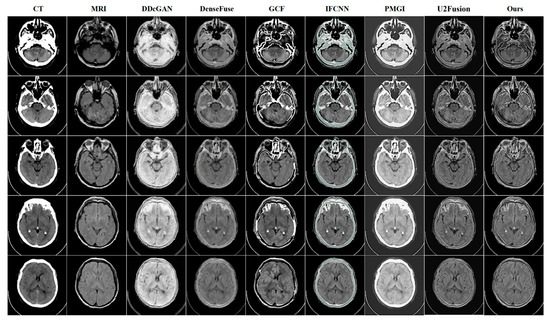

4.3. Quantitative and Qualitative Comparison Results

CT-MRI | DDcGAN | DenseFuse | GCF | IFCNN | PMGI | U2Fusion | Ours |

---|---|---|---|---|---|---|---|

AG↑ | 9.0754 | 5.6772 | 9.1627 | 7.7264 | 7.895 | 6.8957 | 10.1333 |

EI↑ | 91.0206 | 57.5941 | 97.2749 | 81.7838 | 79.8071 | 70.5399 | 99.7997 |

Qabf↑ | 0.3563 | 0.3393 | 0.5682 | 0.5122 | 0.508 | 0.4102 | 0.5402 |

Qcv↓ | 4974.886 | 2599.490 | 4902.781 | 1922.205 | 1592.081 | 2610.5305 | 3376.064 |